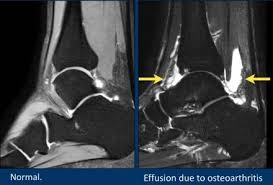

그리고

발목 뒤쪽 통증 중에서

발목을 접질린 뒤에

관절 연골이 찢어져서

관절낭염이 함께 있는 경우가

꽤 많습니다.

위 그림처럼

발목 관절낭염이나

거골하 관절낭염이

동반되어 물이 찬 경우라면

삼출액을 없애고

염증을 치료하는 기간도

더 길어지게 됩니다.